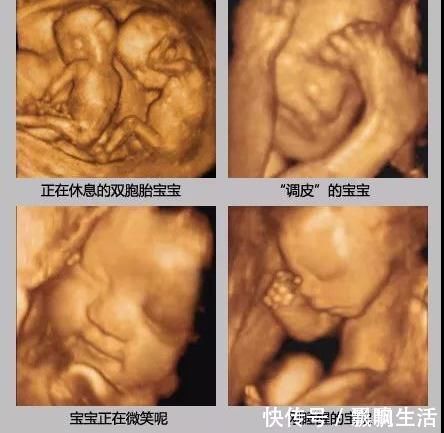

检查时胎儿的“表现”,也可以作为出生后性格的参考,在肚子里就爱搞怪的宝宝,出生后也大多比较淘气。

四维彩超一次不能顺利通过也不用太担心,大多是正常,可能胎儿睡着了、遮挡住了,可以吃点甜食、起来活动下再做一次,也可以另约时间再做。